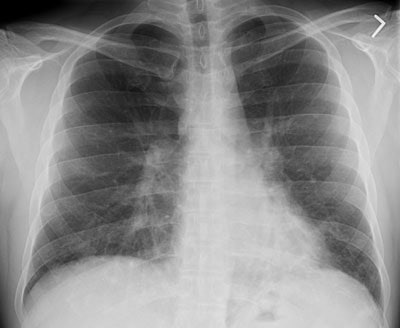

BOOP presenting with pulmonary nodules:

The patient below presented with complaints of cough, malaise, and a low-grade fever. The chest radiograph revealed some patchy left lower lobe airspace disease and vague nodular shadows- particularly in the lower lung zones. A chest CT was performed and demonstrated multiple nodular airspace abnormalities with variable margins. The lesions did not improve despite antibiotic therapy and all cultures were negative. Click images to enlarge. |